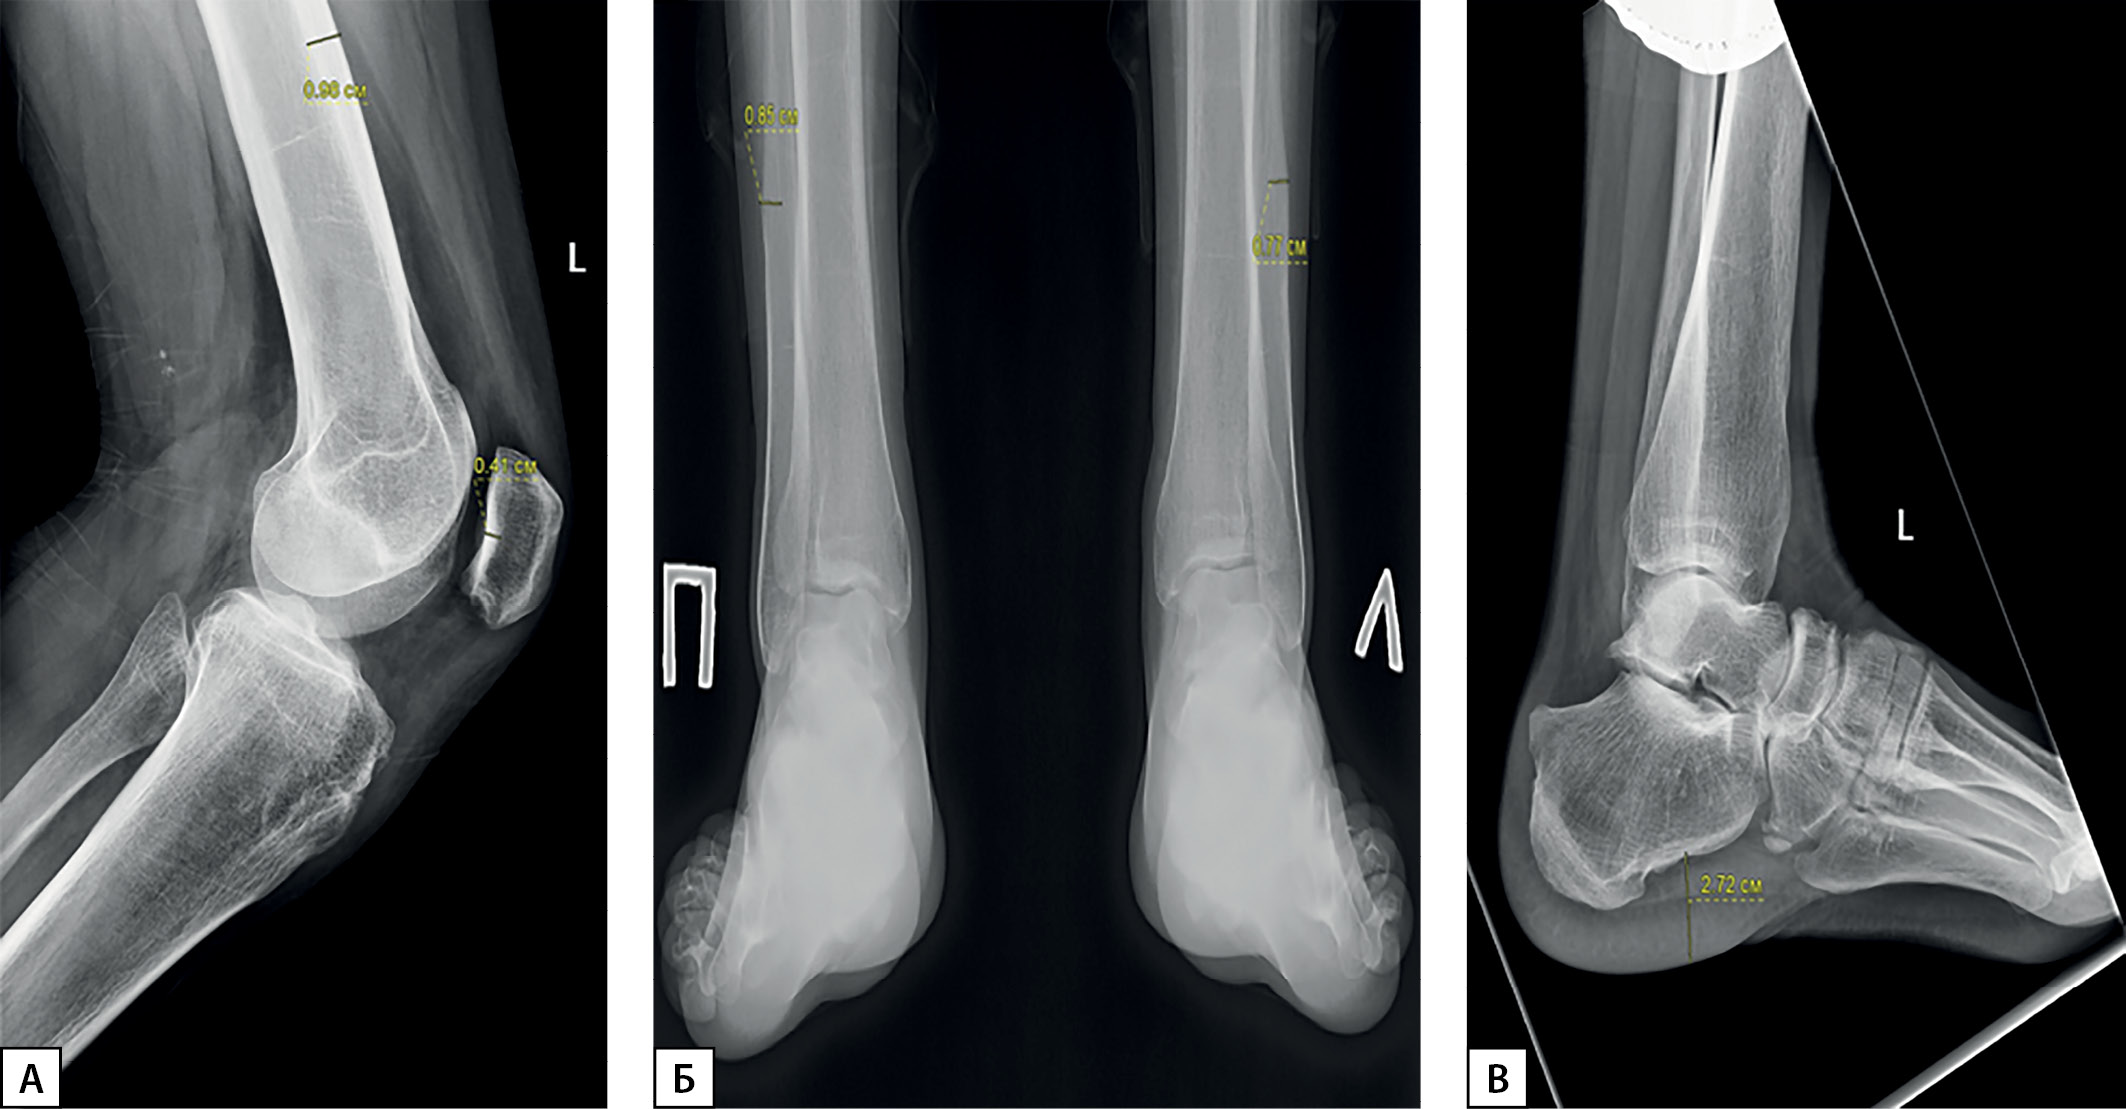

По результатам рентгенографии кистей рук отмечены гипертрофия эпифизов ногтевых фаланг, акроостеолиз, гиперпериостоз диафизов пястных костей и костей предплечья (рис. 3). При проведении рентгенографии коленного сустава выявлены выраженный периостоз диафизов бедренных костей (толщина надкостницы 0,98 cм), средневыраженный периостоз диафизов большеберцовых костей, утолщение внутреннего кортикального слоя надколенника до 0,41 см (рис. 4). По данным рентгенографии голеностопного сустава также отмечаются средневыраженный периостоз, повышение плотности кортикального слоя, гипертрофия пяточного бугра, повышение толщины мягких тканей стопы до 2,72 см слева, гипертрофия задней малоберцовой мышцы, утолщение периоста в нижней трети диафиза малоберцовой кости до 0,85 мм справа и до 0,77 мм слева (рис. 4).

Рисунок 4. Рентгенография коленного и голеностопного суставов.

Примечание. А — рентгенография левого коленного сустава.

Выраженный периостоз диафизов бедренных костей,

средневыраженный периостоз диафизов большеберцовых костей,

утолщение внутреннего кортикального слоя надколенника;

Б — рентгенография голеностопных суставов (вид сзади);

В — рентгенография голеностопного сустава (боковая проекция).

Средневыраженный периостоз, повышение плотности кортикального слоя,

гипертрофия пяточного бугра, утолщение мягких тканей стопы,

гипертрофия задней малоберцовой мышцы,

утолщение периоста в нижней трети диафиза малоберцовой кости.